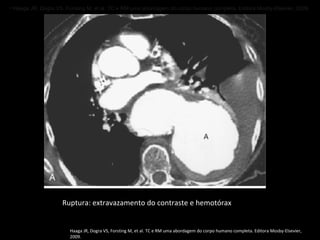

Complicações do aneurisma aórtico

Ruptura é a complicação mais grave;

Taxas de mortalidade entre 70-94%;

Mortalidade no tratamento eletivo: 4%;

Sinais de ruptura: descontinuidade de uma

calcificação circunferencial, presença de crescente

periférico com densidade aumentada, parede

posterior indistinta e extravazamento de meio de

contraste;

O sinal do crescente hiperdenso na parede da aorta

representa hematoma agudo com sangue contido

no interior do trombo do aneurisma;

Diagnosticado melhor na fase sem contraste;

Ruptura da aorta: infiltração da gordura

mediastinal, hemomediastino, hemopericárdio ou

hemotórax;

Formação de fístula: 3ª. Porção do duodeno é o

segmento mais afetado (fístula aortoentérica);

Ruptura: extravazamento do contraste e hemotórax

Haaga JR, Dogra VS, Forsting M, et al. TC e RM uma abordagem do corpo humano completa. Editora Mosby-Elsevier,

2009.